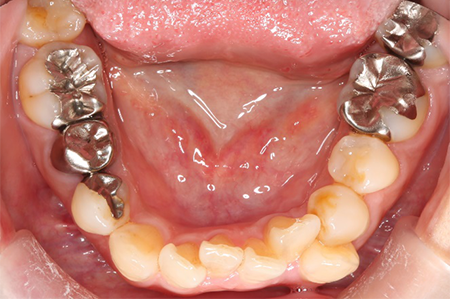

この患者様は長い事歯科医院には通っておらず、下の歯は前歯以外は全て崩壊していることが分かります。

前から見ても歯が欠けてしまい、歯茎も赤く腫れてしまっているのが分かります。

また、奥歯がなくなってからの期間が長かったため、入れ歯が入るスペースが奥にないのが分かります。

様々なことを鑑み、患者様とも何度も話し合いを行い、下の奥歯には必要最低限のインプラントを、他の歯も外科処置を施しなるべく歯を抜かない方法を取りました。

最終的に抜歯した本数は下の歯5本。上の歯に関しては全て残すことが出来ました。